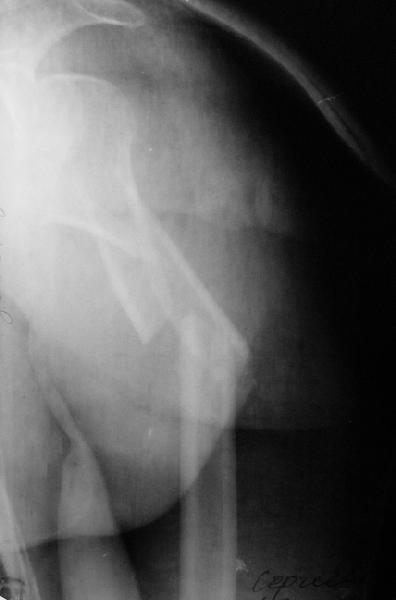

Дорогие коллеги,Мужчина 44 л. упал с крыши дачи 6 августа. Картинки в приложении. Лет 5 назад нде-то оперирован по поводу привычного вывихв этого же плеча.После операции не вывихивал до этой травмы.Как тут лечить? Есть ли шансы на закрытое вправление? Чем лучше фиксировать? Какие меры принять с учетом бывшего и нынешнего вывиха? Заранее спасибо. Dear colleagues, A male 44 y.o. admitted to our unit. Injured at Aug. 6 - fall from 3 m. Images attached. Five years ago was operated somewhere else for recurrent dislocation of thу same shoulder, no data what was done. What would be optimal treatment option? Any chance of closed reduction? What should be done to address the current and past dislocations? THX.

I would recommend an initial attempted closed reduction in the OR with fluoroscopy. It is important that this is done in a controlled fashion to make sure you are not further displacing the head and leaving it behind. If

you can get it reduced then you will have a much better ability to understand the fracture and possible glenoid involvement. I think regardless

of getting the humeral head reduced this fracture should be managed operatively with plate fixation of the tuberosity fragment and a combination of lag screw and plate fixation of the proximal shaft extension. My concern is that treating it conservatively after closed reduction will lead to issues of instability and malunion given the size of the tuberosity fragment and past history.

I would also not be surprised if there was some glenoid issues related to the prior instability. It is difficult to tell on the provided xrays. Either a CT scan or an Axillary view should be done to assess this prior to definitive surgery.

This is an anterior fracture/dislocation with shaft extension-no chance for closed reduction-probably contraindicated, especially since the injury is now 19 days old. We do these supine on a radiolucent table with an arm board extension-you now have an unobstructed radiographic view of the entire upper extremity both AP and lateral with excellent axillary views of the glenohumeral joint to assess your reduction and screw placement. This is the perfect indication for a locking plate via the traditional deltopectoral approach. Use the biceps tendon to stay anatomically oriented during the approach and be sure to check the rotation post plate application. In general, we have not performed any soft tissue stabilization procedures during the fixation, may stay away from external rotation past neutral during rehab and early motion protocol. This one should do fine.